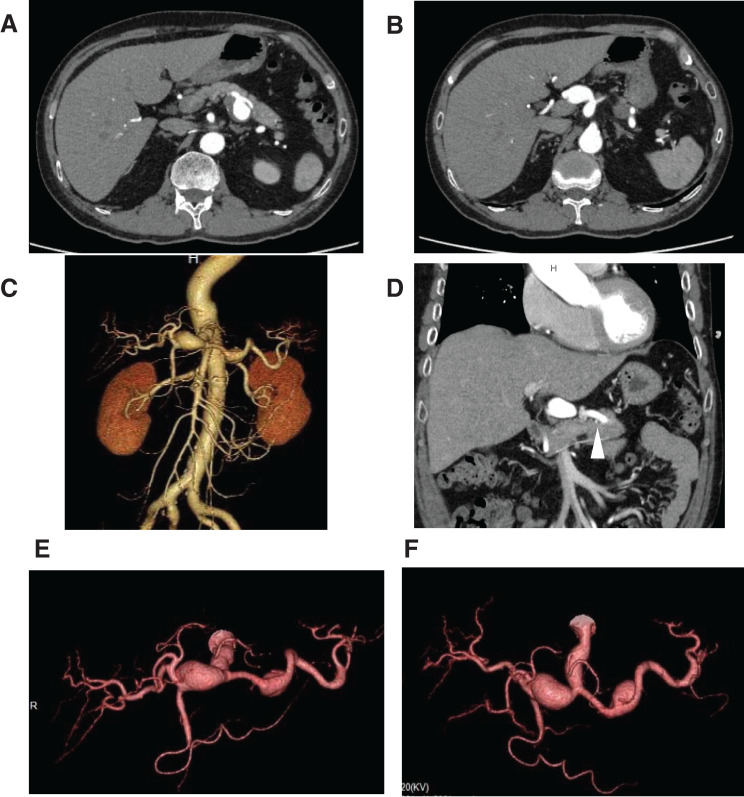

A 59-year-old patient was undergoing careful monitoring of an isolated superior mesenteric artery dissection discovered 6 years prior. He was admitted after outpatient imaging revealed multiple visceral aneurysms including common hepatic and splenic artery aneurysms that had enlarged. Based on anatomical reasons and the past history, the splenic artery aneurysm was treated with endovascular therapy, while the common hepatic artery aneurysm was resected, and blood flow reconstruction was performed. The patient was discharged without any complications. Visceral artery aneurysms have diverse locations and morphologies, illustrating the importance of treatment strategies that consider the blood flow to the organs.